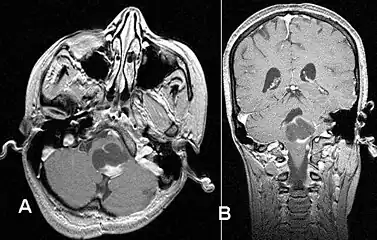

Stereotactic MRI brain scan showing a recurrent postoperative brain stem cystic pilocytic astrocytoma.

Pilocytic astrocytoma in the hypothalamic region.

T1-weighted coronal MRI image postcontrast showing heterogeneous contrast enhancement within the presumed tectal plate glioma